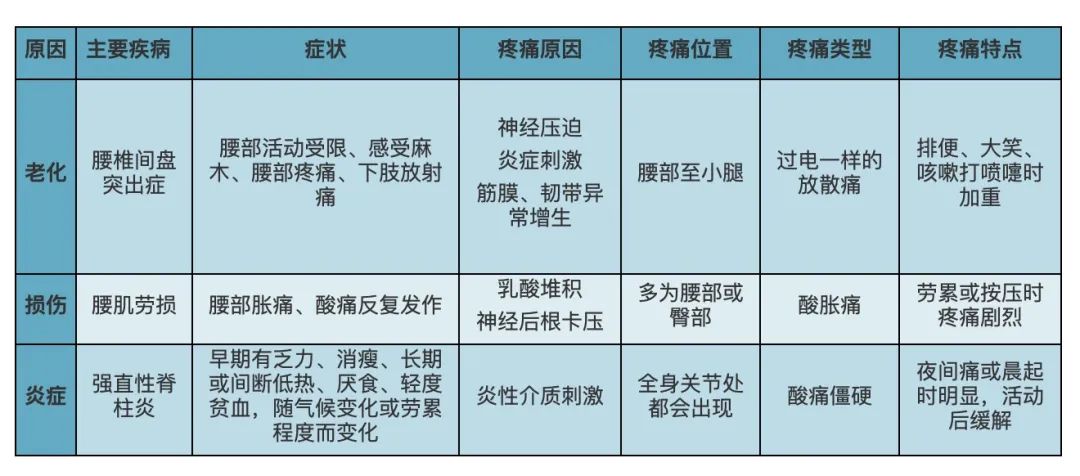

引起腰腿疼的原因及相关疾病有哪些?